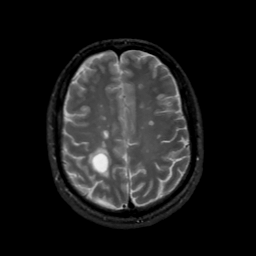

MR Study #7, March 24, 1991 -- Slice #36